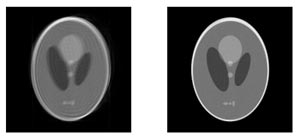

Motion affected Shepp-Logan head phantom (left) and corrected version using TRELLIS (right)